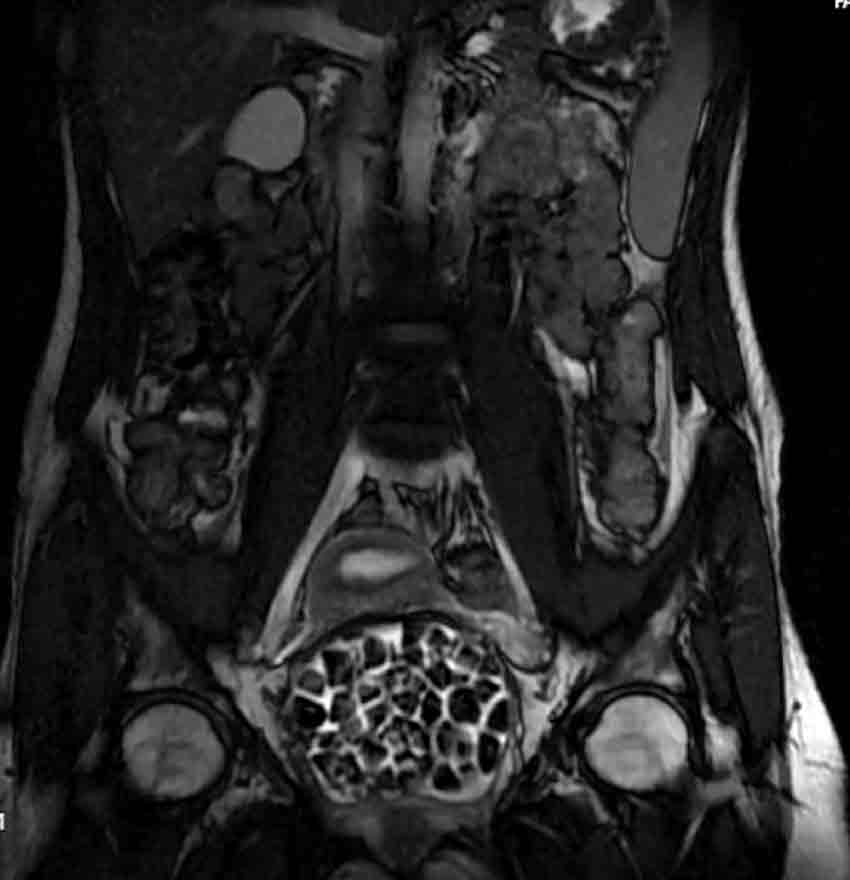

Hastasının durumuna yönelik konuşan Üroloji Uzmanı Doç. Dr. Erkan Erkan, "Hastamızın 2004 yılında doğduğunu ardından doğar doğmaz ekstrofi vezika dediğimiz 50 binde bir görülen bir anomaliden dolayı art arda ameliyatlar geçirdiğini öğrendik. 10 yaşında yine bir ameliyat geçirmişti, gerekli görüntüleme ve tetkiklerimizi yaptırdık. Normalde mesanesinin olması gereken yerin hemen arka kısmında taşlarla dolu bir kese olduğunu gördük, bunun üzerine ek görüntülemeler; MR çektirdik. Hastamız çelişkili açıklamalar almıştı, kendi radyolojik kliniğimiz ve edindiğimiz konsültasyonlarda taşların mesanede değil vajinal boşlukta oluştuğunu düşündük, bir planlama yaptık. Kadın doğum hocamızın da çabasıyla taşları tamamen temizledik ardından ileride normal bir hayat sürmesi bakımından oraya plastik cerrahi yaptık. 287 adet taş çıkardık, pratikte gerçekten görünce çok şaşırdık çünkü bu aynı zamanda literatürde çok nadir görülen bir olay. Biz ameliyata hazırlanırken de teorik olarak biraz araştırdık. Literatürde gördüğümüz kadarıyla buna benzer bu tanıma uyan bir vaka vardı. Literatürde sanırım yayınlanmış 2’nci vaka olacak. Farkındalık çok önemli, bilinçli bir hastamız vardı. Doğumsal anomaliyle doğan çocuklarımızda ileride bunlara bağlı bazı sıkıntılar çıkabileceğinin öngörülmesi lazım. İlgili tedavilerini alsalar bile düzenli takiplere gelmeleri gerekiyor. İleride eğer dikkat etmezse ki zannetmiyorum, tekrarlayabilir. Bu rahatsızlık ekstrofi vezikal epispadias durumu çok nadir bir durum" dedi.

Genç kızın uzun süredir devam eden karın ağrısı olduğunu söyleyerek sözlerine başlayan Jinekolojik Onkoloji Uzmanı Op. Dr. Emin Erhan Dönmez, "Mesane taşları olduğu düşünülerek daha büyük bir hastaneye refere edilmiş. Aramızda mini bir konsey yaparak muayene ettik. Vajen bir hazne görevi görerek orada durağan bir idrar, uzun süre beklediği için idrar içindeki minerallerde çökerek taşlar oluşmuş. Mesanedeki idrarın vajene akmış olabileceği ve vajende göllenen idrar nedeniyle taşların burada oluşacağını düşündük, ameliyatımızı planladık. Ameliyata tanı amaçlı girmiştik, sistoskopi (Mesane gibi idrar yollarını kapsayan kısımlardaki rahatsızlıkların teşhis ve tedavisinde kullanılan endoskopik bir yöntem) dediğimiz ameliyatı Erkan Hocam ile birlikte gerçekleştirdik. Önce mesaneyi bir görüntüledik, mesane tabanına yaklaşık 2-3 cm’lik bir alandan vajene fistülize olduğunu gördük. Mesaneden vajene geçtiğimiz esnada tüm vajenin taşlarla dolu olduğunu gördük. Tanı amacıyla girdiğimiz ameliyatta her şey de olağan gittiği için tedaviye geçtik. Taşların çıkabileceği kadar bir genişlik sağladık. Daha sonra yaklaşık en büyüğü 2,5 cm boyutlarında olan, irili ufaklı 287 tane taşı ameliyat esnasında çıkarmış olduk. Taşların tekrarlamaması için idrarın göllenmemesi, en azından dışarıya rahatça boşalabilmesi için vajinal rekonstrüksiyonu sağladık. Ameliyatta da herhangi bir problem yaşamadık. Literatürü Erkan Hocam ile birlikte değerlendirmiştik. Primer olarak vajende birikmiş olan bu kadar çok sayıda taşla ilgili bir makale görmedik, rastlamadık" dedi.